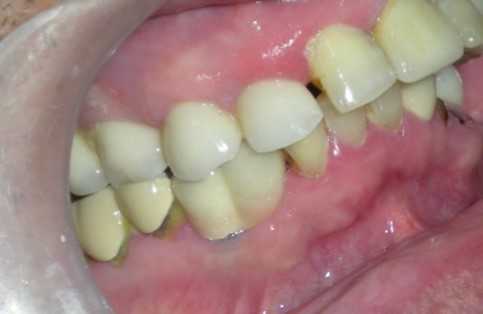

The separator spray (Detax, Germany) was applied around the impression copings (Figure 7) before the application of artificial gingiva (Esthetic mask, Detax, Germany) for easy separation of artificial gingiva from impression material as both are silicones. The artificial gingiva was applied around impression copings and the impression was poured with type IV gypsum product ((Kalstone; Kalabhai Karson Pvt. Ltd. India) to obtain the master cast (Figure 8), which, with a soft tissue gingival mask, will allow the restorative dentist and technician to choose the ideal abutment and technique for the case. Further , the accuracy of the impression was verified with verification jig. the verification jig should fit passively on the cast as well as in patient mouth. After verification jig trial, the prosthesis (two joined PFM crowns, Figure 9 and Figure 10) was fabricated over two modified castable UCLA abutments (PLA-R straight plastic abutments, AlphaBio, Israel). The final prosthesis was cemented with chemical cure resin cement.

Figure 10.Definitive Prosthesis

Definitive Prosthesis